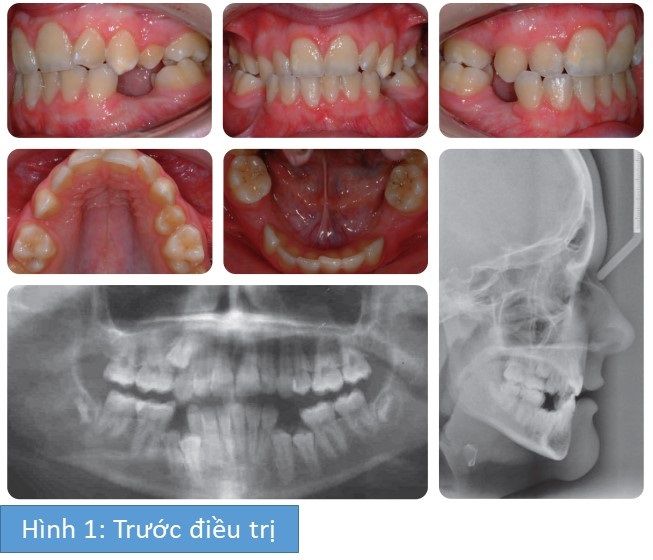

Phân tích case: Niềng răng cho bệnh nhân 14 tuổi có nhiều răng hàm nhỏ không mọc

Bệnh nhân nữ 14 tuổi có tương quan răng cửa hạng III trên nền xương hạng III phức tạp bởi:

- Nhiều răng hàm nhỏ không mọc

- Thiếu các răng hàm nhỏ thứ 2 hàm trên

- Chen chúc nặng ở cả 2 cung hàm